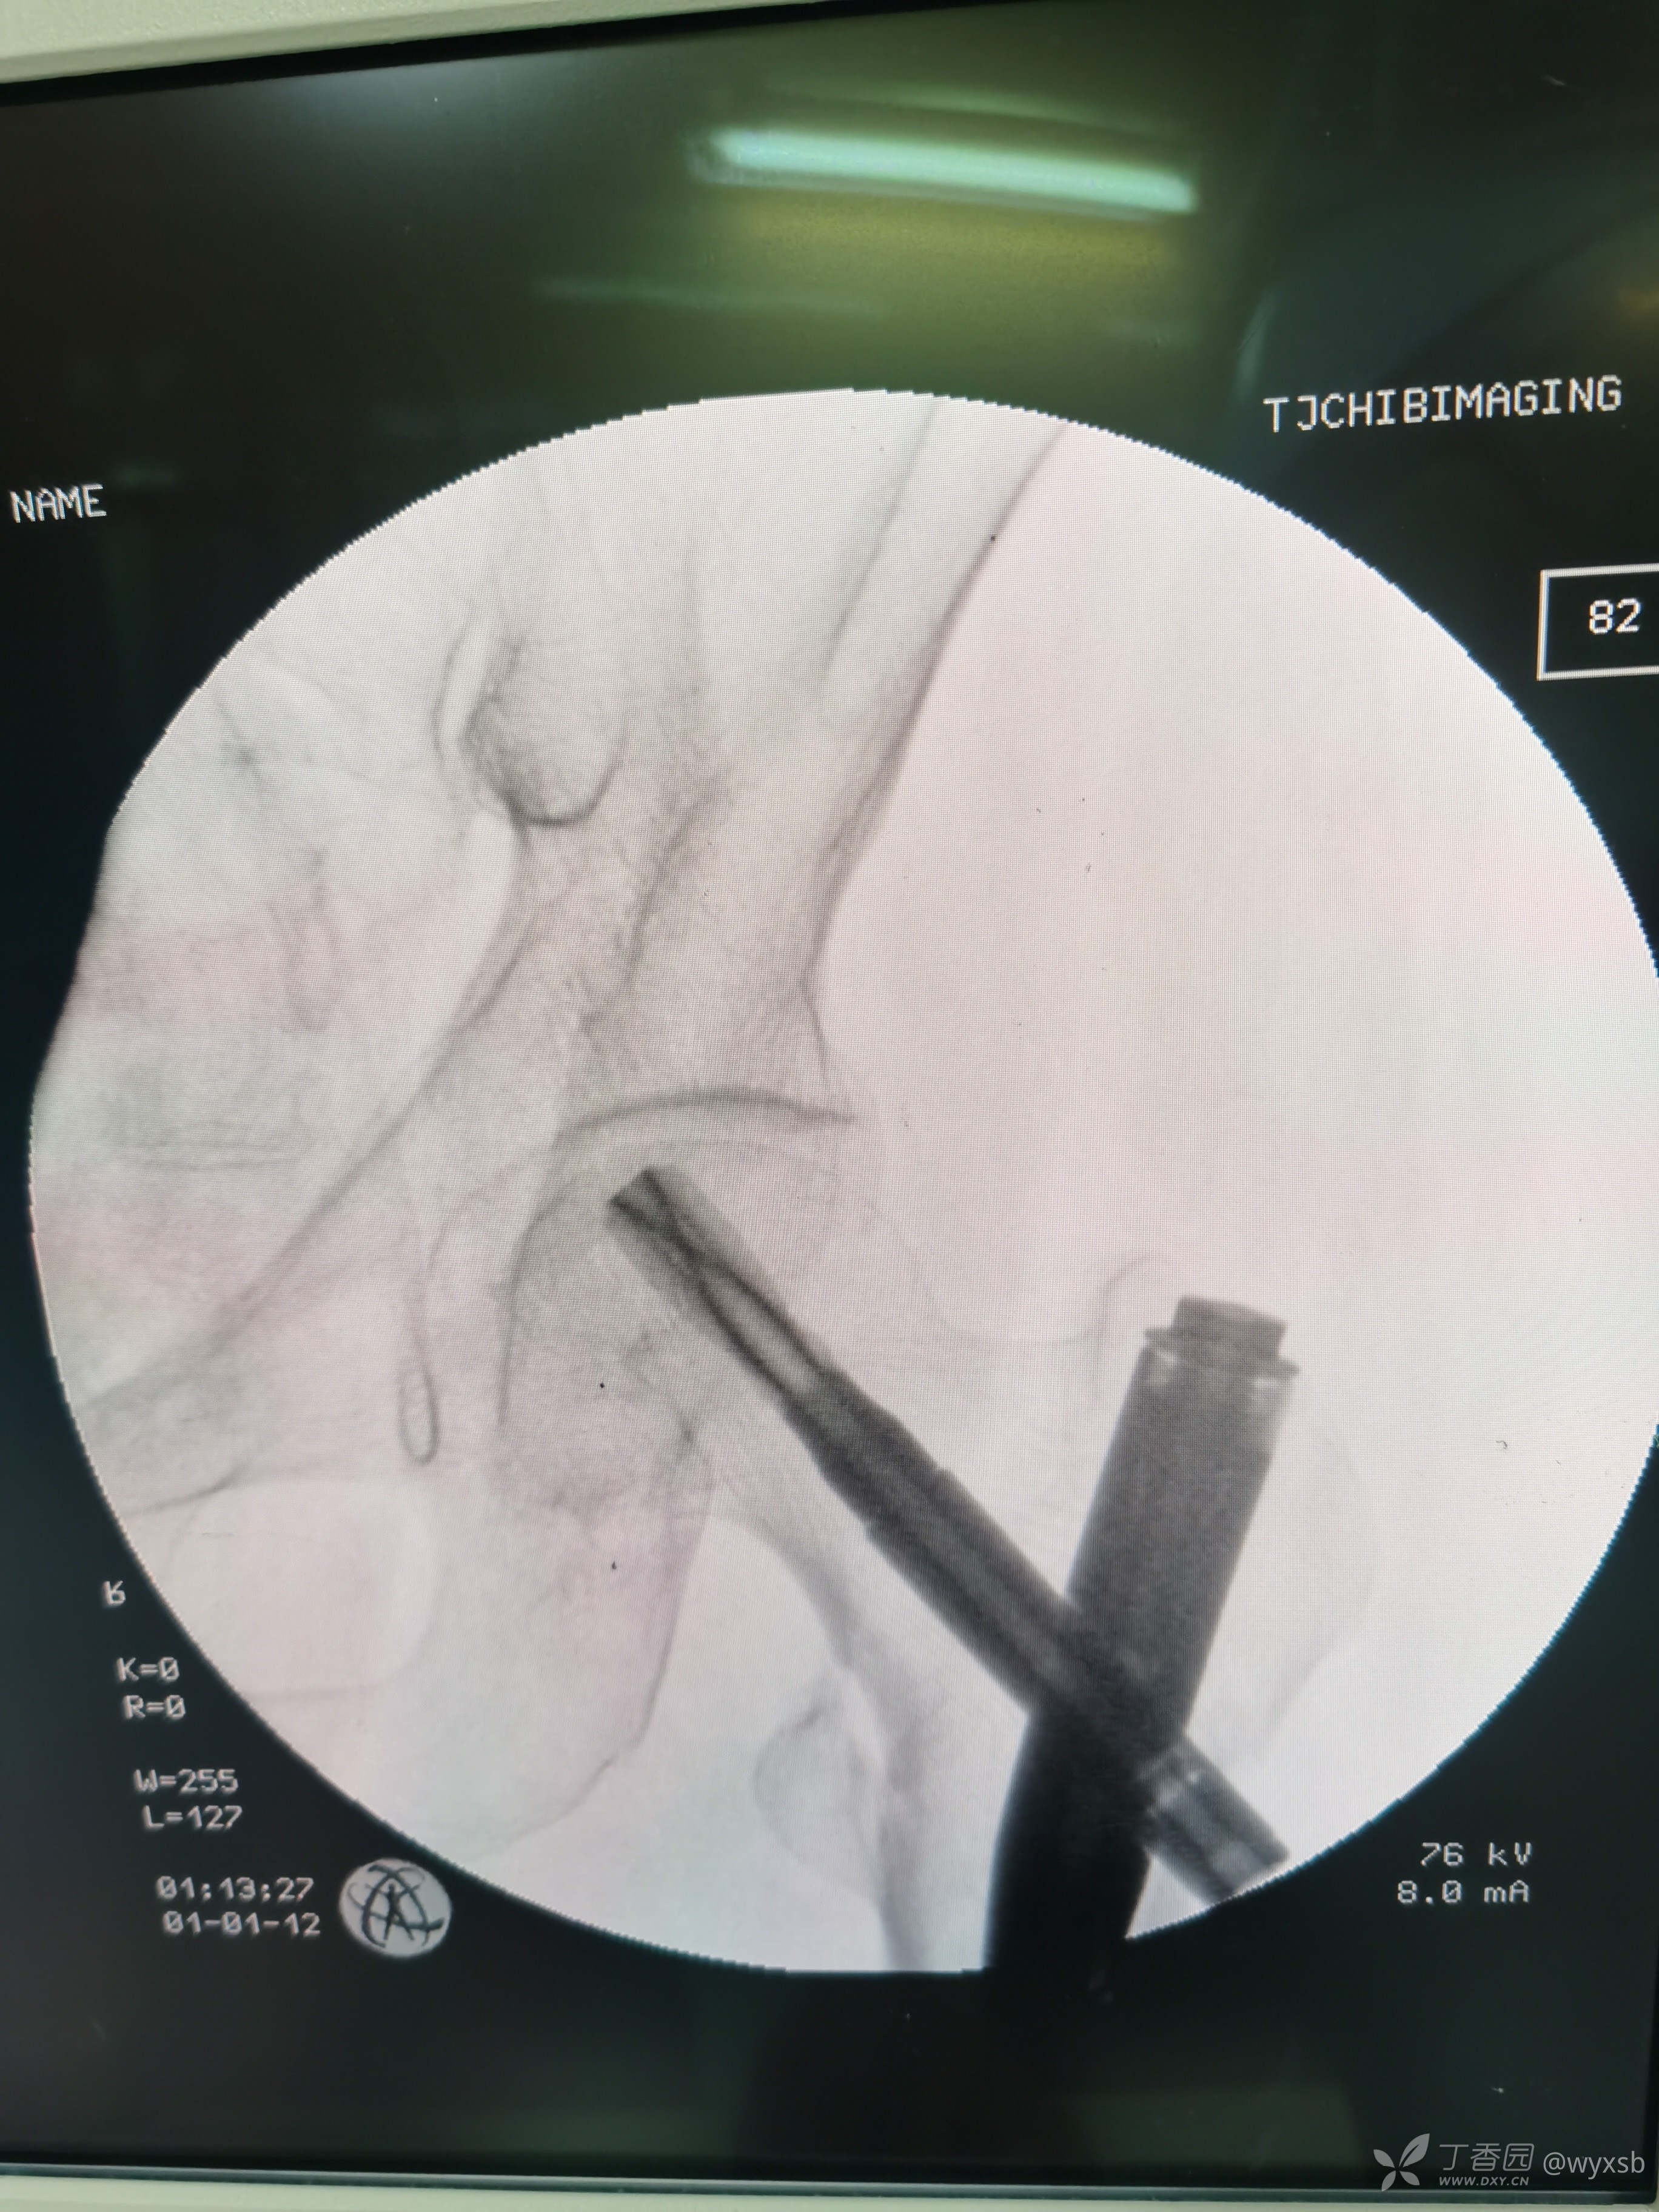

术中植钉情况

术中透视